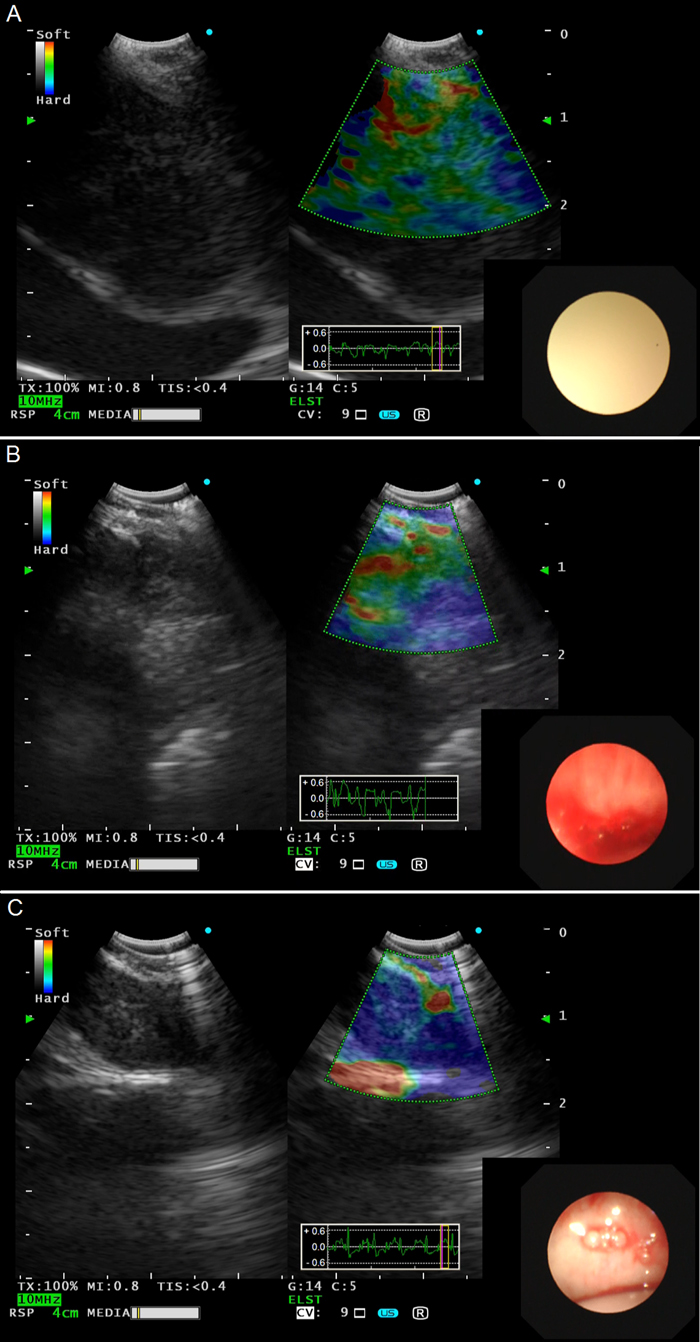

Figure 4: Representative lymph nodes on EBUS elastography. A. Type 1: dominant colors were green, yellow or red. B. Type 2: part blue, part green, yellow or red. C. Type 3: dominant color was blue. EBUS, endobronchial ultrasound.

Real-time EBUS B-mode and elastography were recorded as digital movies prospectively. Strain elastography was used to evaluate lymph nodes in our study. Ultrasonic criteria of EBUS B-mode and vascular pattern on power Doppler included size, shape, border distinction, echogenicity, CHS-CBV and coagulation necrosis, sighs that have been previously demonstrated to predict malignancy or benign mediastinal lymph nodes [16]. After recording the movies of EBUS B-mode ultrasound criteria, the procedure was switched to strain elastography mode and all lymph nodes that were candidates for EBUS-TBNA were evaluated by strain elastography. The elastography image was generated by vascular pulsations and respiratory movement as the result of tissue compression. After comparing the scanned area with the surrounding normal tissue, elastography images were reconstructed and translated into a color signal that was overlaid on the B-mode image. Blue was indicated to represent hard tissue; otherwise, green and yellow/red were indicated to represent mediate, soft tissue, respectively. Based on the dominant colors and their distributions in the target lymph nodes, elastographic patterns were classified into 3 types as previously described and shown in Figure 4 [25]: Type 1 (Figure 4A), dominant colors were green, yellow or red; Type 2 (Figure 4B), part blue, part green, yellow or red; Type 3 (Figure 4C), dominant color was blue.